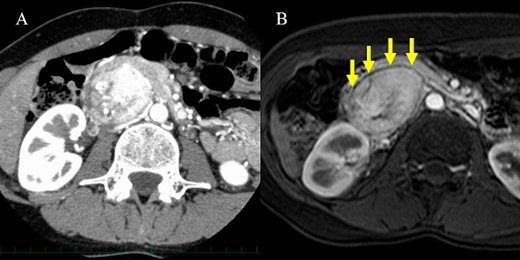

A 61-year-old man underwent a positive fecal occult blood test and was diagnosed with adenocarcinoma of the transverse colon based on colonoscopy and biopsy results. During the preoperative evaluation, a hypervascular neoplasm located posterior to the pancreatic head was incidentally detected on abdominal contrast-enhanced CT scan (Fig. 2A). The arterial phase of the contrast-enhanced CT scan showed a 6.5 × 3.5 cm2 heterogeneous mass with fat plane between the mass and pancreas while a beak sign was not observed. The patient’s medical history included hypertension, and PGL was suspected based on CT scan images and medical history. His laboratory data were unremarkable except for high urinary metanephrine levels. Metaiodobenzylguanidine (MIBG) scintigraphy was also performed and showed an abnormal uptake at the site of the neoplasm (Fig. 2B). Thus, the patient was preoperatively diagnosed with PGL. According to the intraoperative findings, combined resection with pancreatectomy was unnecessary (Fig. 3). Hence, he underwent tumor resection for PGL and right hemicolectomy for transverse colon cancer. Histopathological and immunohistochemical findings confirmed the diagnosis of PGL (Fig. 4). The patient had an uneventful course except for a mild superficial surgical site infection (Clavien–Dindo grade I complication), and no tumor recurrence was observed for 24 months.

Computed tomography scan and metaiodobenzylguanidine scintigraphy. (A) Imaging findings showing a well-defined mass with heterogeneous enhancement located adjacent to the pancreatic head. A fat plane was identified between the mass and pancreas (arrows). (B) Metaiodobenzylguanidine scintigraphy revealed accumulation at the same site of the abdominal tumor.